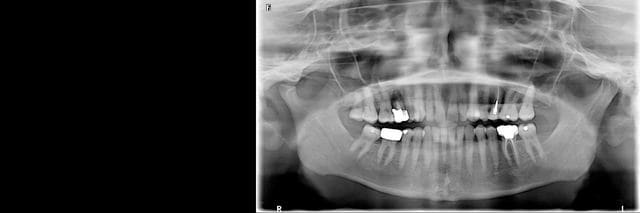

Et finalement: la dent, l'implant est pas parfaitement posé mais le résultat global est satisfaisant.